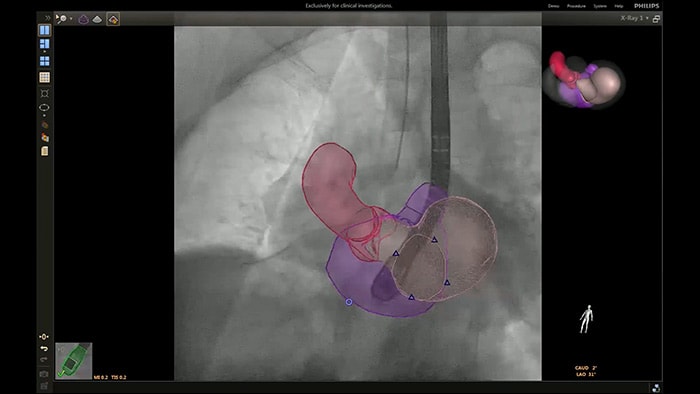

En el centro de nuestra suite, la exclusiva solución EchoNavigator es el ejemplo emblemático del compromiso de Philips con la multimodalidad y la integración del flujo de trabajo, aporta lo mejor de ambos mundos del líder de la industria en soluciones cardíacas intervencionistas de rayos X y ecografía.

Implementación de la superposición de la ETE 3D en vivo de la oclusión de la LAA con EchoNavigator

Segmentación del modelo EchoNavigator 3D

Guía de punción transeptal mediante EchoNavigator

Optimización de la vista de la válvula mitral con modelos de corazón EchoNavigator

Optimización de la vista de la válvula tricúspide con modelos de corazón EchoNavigator

Visualización de las válvulas mitral y aórtica con modelos cardíacos EchoNavigator